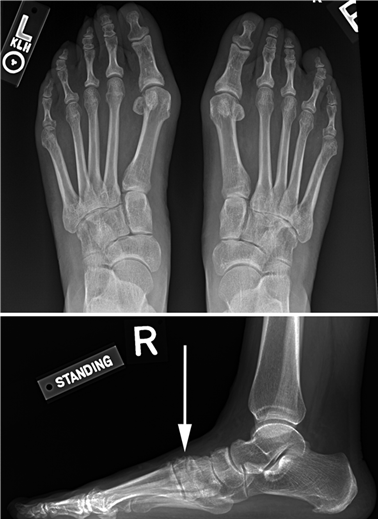

Weight-bearing anteroposterior (AP), lateral, and sesamoid axial radiographs are mandatory. On the AP view, the surgeon measures the Hallux Valgus Angle (HVA, normal < 15°), the Intermetatarsal Angle (IMA, normal < 9°), and the Distal Metatarsal Articular Angle (DMAA). The lateral view is scrutinized for Meary's angle (talo-first metatarsal angle) to identify midfoot collapse, as well as the presence of dorsal osteophytes indicative of hallux rigidus. The sesamoid axial view is critical for assessing the degree of sesamoid subluxation and the integrity of the crista.

| Transfer Metatarsalgia | 5 - 15% | Excessive shortening or dorsal elevation of the first metatarsal (malunion). | Orthotic management (metatarsal pads); Weil osteotomies of lesser metatarsals; Plantarflexing 1st TMT revision. |

Clinical & Radiographic Imaging Archive